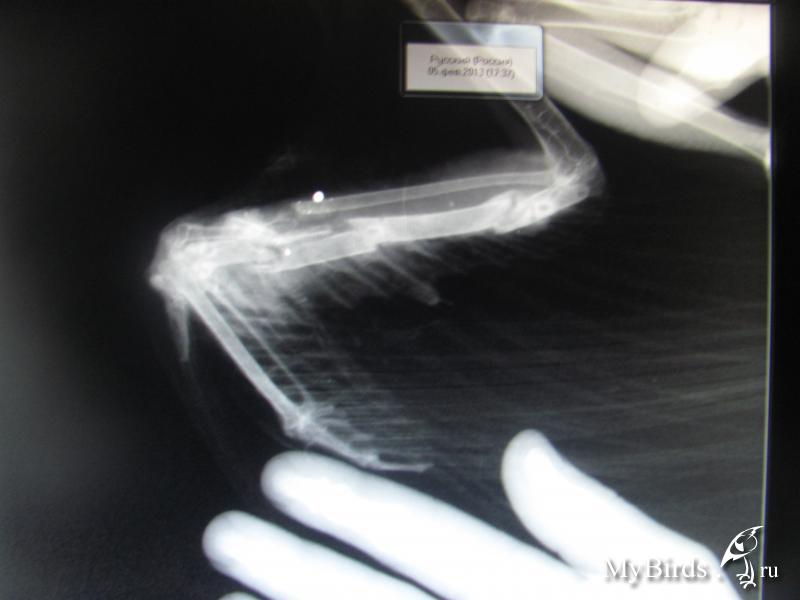

Забота о питомцах: рентген лапок волнистого попугая